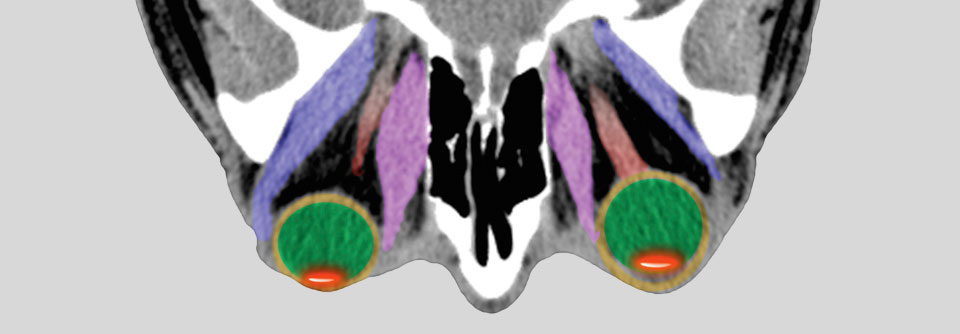

Endokrine Orbitopathie mit Lidretraktion und Exophthalmus. Endokrine Orbitopathie mit Lidretraktion und Exophthalmus. © wikipedia.org/Jonathan Trobe, M.D. - University of Michigan Kellogg Eye Center, CC BY 3.0

Mit einer jährlichen Inzidenz von 20 bis 50 Fällen pro 100 000 Einwohner ist der M. Basedow die häufigste Ursache der Hyperthyreose, schreiben Dr. Terry J. Smith von der University of Michigan Medical School, Ann Arbor, und Mitarbeiter. Die Erkrankung kann in jedem Alter auftreten, besonders häufig manifestiert sie sich aber bei 30- bis 50-Jährigen, wobei es Frauen sechsmal häufiger trifft als Männer. In bis zu 50 % der Fälle liegt eine klinisch bedeutsame Ophthalmopathie vor, die bei einem kleinen Teil der Patienten sogar den Visus bedrohen kann.